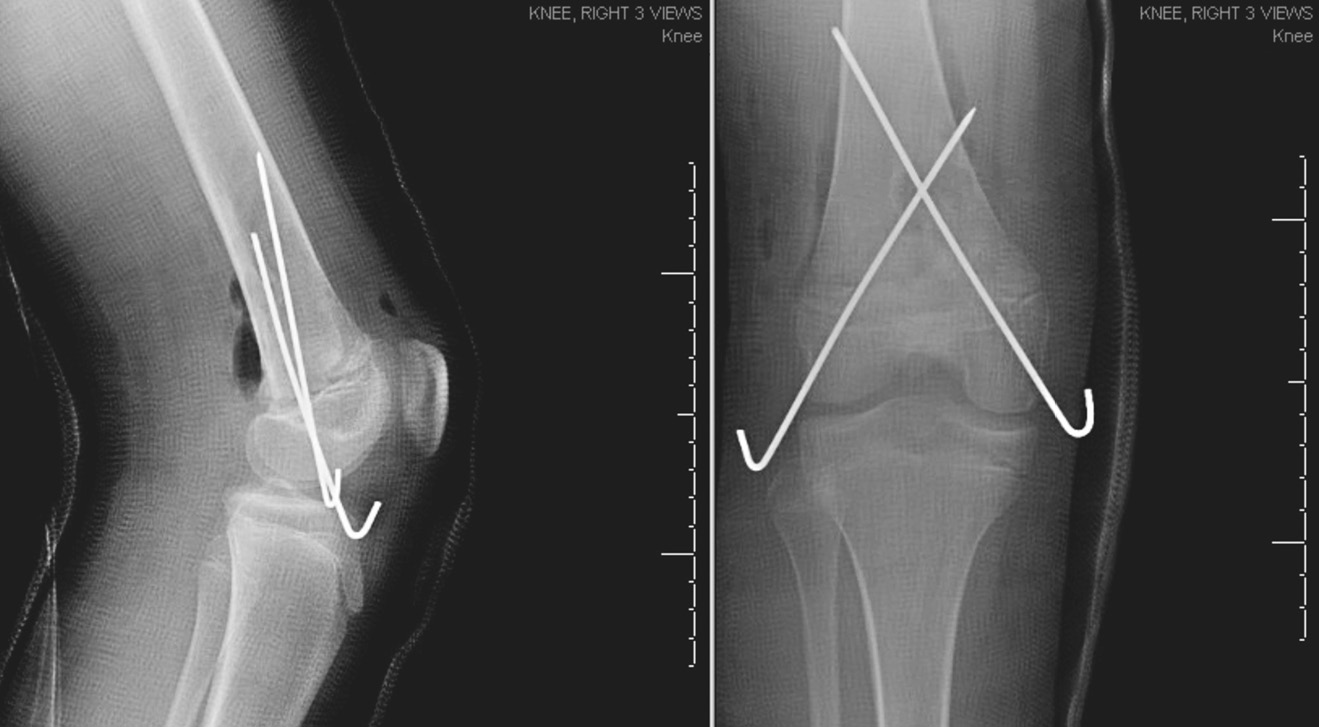

Был выполнен заднебоковой разрез в области дистального отдела правого бедра. После тщательного промывания 9 л изотонического раствора натрия хлорида была высвобождена ущемленная надкостница и выполнена репозиция перелома. Перелом зафиксирован в удовлетворительном положении с помощью перекрестной установки спиц через дистальный эпифиз бедренной кости. Нормальное кровоснабжение было подтверждено допплерографически, и рана ушита. Пациентке был наложен длинный гипс без возможности опоры на ногу. На послеоперационных рентгеновских снимках видна удовлетворительная репозиция дистальной части бедра (рис. 3). Поскольку пациентка была иногородней и ее дом находился в 3 часах езды от больницы, врачи рекомендовали ей остаться в больнице на 2 дня во избежание развития компартмент-синдрома или нейрососудистых нарушений и для завершения 48-часового введения цефазолина внутривенно. Затем пациентка была выписана домой. Девочка оставалась в гипсе без опоры на ногу в течение 4 нед. Спицы были удалены через 6 нед. По истечении 6 мес. пациентка прошла контрольное обследование, которое показало, что она не испытывает затруднений в движении. Восстановление прошло успешно, и ребенок снова смог посещать уроки физкультуры. На заключительных рентгенологических снимках через 6 мес. репозиция сохранялась. Пациентка наблюдалась в течение 2 лет, при этом у нее не было отмечено угловой деформации конечности или различия в длине ног.

Рис. 3. Рентгенограмма правого коленного сустава в переднезадней и боковой проекциях после открытой репозиции и внутренней фиксации. Видна нормальная репозиция с фиксацией двумя спицами, перекрестно установленными через эпифиз

При любом переломе у детей осложнения после травмы могут полностью проявиться спустя месяцы или годы. В молодом возрасте восстановление происходит быстрее, но при этом может наблюдаться неравномерный рост ног. Мы рекомендуем проводить тщательное и длительное наблюдение пациента с целью выявления любых задержек роста дистальной части бедра. Мы также продлили срок фиксации в гипсе без применения опоры на ногу до 4 нед. и удалили спицы через 6 нед., чтобы обеспечить нормальное сращение перелома.